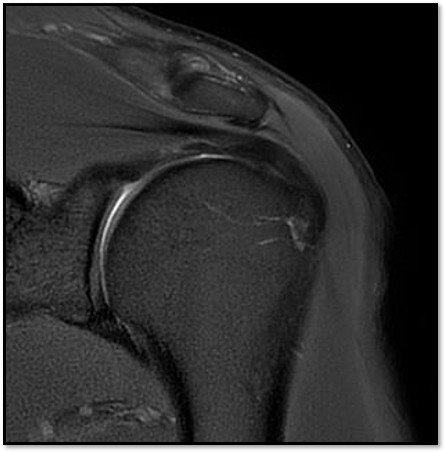

MRI를 검토해보았습니다. 확실히 회전근개 극상건에 부분파열이 있었습니다.

진단:

MRI: 극상건 관절면측 부분파열 (약 40%)

파열 양상: 가로 파열, 깔끔함

MRI: 극상건 점액낭면측 부분파열 (약 35%)

인대 얇아짐 소견

16주 후 MRI: 인대 두께 증가 확인

MRI: 극상건 부분파열 (약 25%)

파열 양상: 가로 파열, 경미